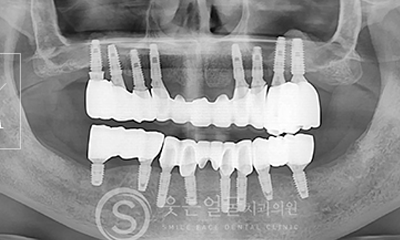

While the initial implant procedure is crucial, revision surgery may sometimes be necessary due to issues such as incorrect placement,infection, or bone loss.

SMILE FACE DENTAL CLINIC leverages extensive clinical experience and precise diagnostic equipment to accurately identify the causes of problems with existing implants and to perform safe, systematic revision procedures.

Implant

Before & After Photos